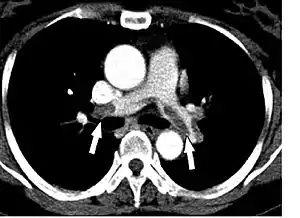

Спіральна комп'ютерна томографія

Спіральна комп'ютерна томографія за методикою проведення та затратами є більш простішим обстеженням та рівнозначним по інформативності з селективною контрастною ангіопульмонографією. Цей метод дозволяє виявляти тромби безпосередньо у просвіті судин. Чутливість односпіральної КТ становлять близько 70 %, а специфічність — 90 %. Впровадження в клінічну практику мультиспіральної КТ дозволило підвищити чутливість обстеження до 83 %, а специфічність до 96 %.[14] На думку групи експертів Європейського товариства кардіологів, для хворих з високим ризиком ТЕЛА достатньо проведення односпіральної КТ, а для хворих із низьким та середнім ризиком ТЕЛА необхідне проведення мультиспіральної КТ для більш точної верифікації діагнозу.[15]